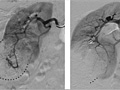

Angiogram

An angiogram is an X-ray test that uses dye and a camera to take pictures of the blood flow in an artery or a vein. An angiogram can be used to look at the arteries or veins in the head, arms, legs, chest, back, or belly. This test is done to look for problems in the arteries or veins.

During an angiogram, the doctor will put a thin, flexible tube into a blood vessel in your groin or arm. This tube is called a catheter. The doctor guides the tube to the blood vessel that will be studied. Then a dye is injected through the tube to make the area easier to see. X-rays or pictures are taken of the area.

When the catheter is in place, the dye is injected through it. You may be asked to take a breath and hold it for several seconds. Several X-ray pictures will be taken one after another. These will be available right away for your doctor to look at. You need to lie very still so the pictures are clear. More pictures may be taken.